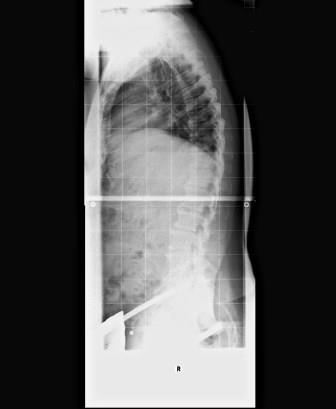

Hab mal mein aktuelles Röntgenbild angehängt. Die 55° sind meines Erachtens nach von Dr. Hoffmann etwas optimistisch vermessen worden. Mir kommt der Winkel doch noch etwas größer vor.

Die Termine für die manuelle Therapie habe ich vereinbart. Mal sehen, ob sich da was tut.

- Röntgenbild vom 27.04.2017